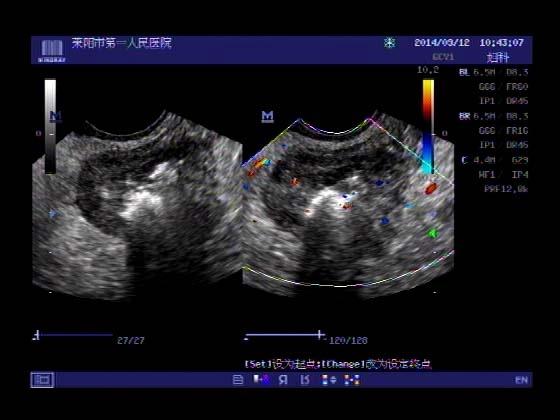

超声入门贴353-----直肠癌伴肝转移

女,66岁